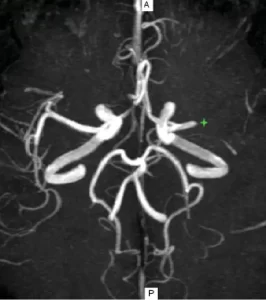

Imagen de angio resonancia cerebral

Angio resonancia cerebral mostrando el sistema vascular

La angioresonancia es una técnica de imagen no invasiva que utiliza campos magnéticos y ondas de radio para obtener imágenes detalladas de los vasos sanguíneos. Este procedimiento es fundamental para diagnosticar enfermedades vasculares, como aneurismas, estenosis y malformaciones arteriovenosas.